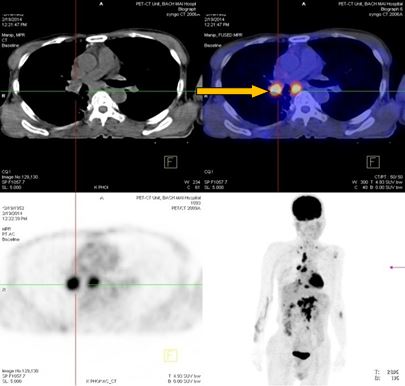

-          Bệnh nhân đã được tiến hành chụp PET/ CT đánh giá, kết quả:

+ Vùng phế quản gốc phải có khối KT 2,4x1,7cm, tăng hấp thu F-18 FDG, max SUV=8,50. Hạch trung thất kích thước lớn nhất 3,1x3,5cm, max SUV=10,29

- Trước điều trị: Khối u 2,4x1,7cm, max SUV=8,50. Hạch dưới carina KT 3,1x3,5cm, max SUV=10,29

- Sau điều trị 4 thángKhông rõ u, không có hạch trung thất